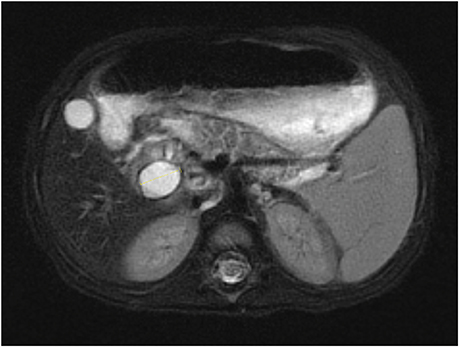

After admission, a follow-up MRCP (Fig. 1) and ultrasonography (Fig. 2) revealed a 1.7 cm-sized cystic lesion around the CBD and duodenum showing no definite communication with the CBD, indicative of a duodenal duplication cyst causing biliary obstruction or an unusual choledochal cyst or choledochocele. To evaluate the relationship between the cystic lesion and the duodenum, a upper gastrointestinal series and computed tomography were taken and showed mild narrowing at the proximal duodenum with no evidence of communication between the cyst and the duodenum. However, the structural continuity between the cyst and the biliary tree still remained unclear, so a percutaneous transhepatic cholangiography (Fig. 3) was performed and revealed a cystic lesion located at the confluence level between the common hepatic duct (CHD) and cystic duct (CD) with possible communication with the CD, highly suggestive of Todani type II choledochal cyst.

Fig. 1

Magnetic resonance cholangiopancreatography showing 1.7 cm-sized cystic lesion.